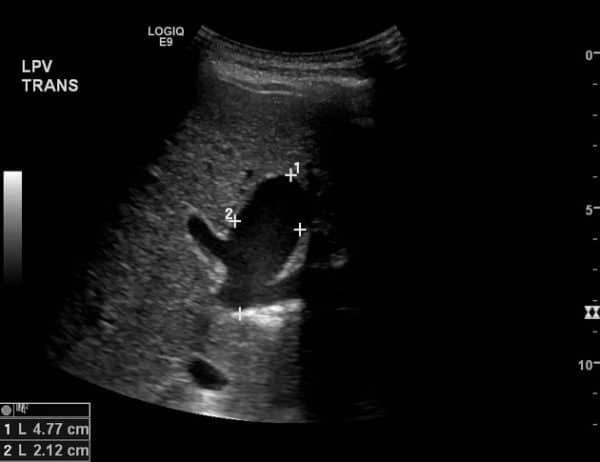

Phình TM cửa - Ảnh 3

Phình TM cửa

» Thông tin: Nam giới – 90 tuổi.

» Lâm sàng: Kiểm tra sức khỏe.